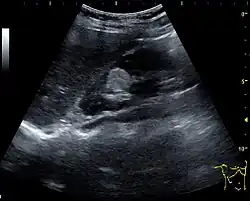

Figure 8. Cortical solid mass, which later was shown to be renal cell carcinoma. Measurement of the solid mass on the US image is illustrated by '+' and a dashed line.[1]

Figure 9. Renal cell carcinoma with both cystic and solid components located in the cortex. Measurement of tumor on the US image is illustrated by '+' and a dashed line.[1]

A solid renal mass appears in the US exam with internal echoes, without the well-defined, smooth walls seen in cysts, often with Doppler signal, and is frequently malignant or has a high malignant potential. The most common malignant renal parenchymal tumor is renal cell carcinoma (RCC), which accounts for 86% of the malignancies in the kidney. RCCs are typically isoechoic and peripherally located in the parenchyma, but can be both hypo- and hyper-echoic and are found centrally in medulla or sinus. The lesions can be multifocal and have cystic elements due to necrosis, calcifications and be multifocal (Figure 8 and Figure 9). RCC is associated with von Hippel–Lindau disease, and with tuberous sclerosis, and US has been recommended as a tool for assessment and follow-up of renal masses in these patients.[1]